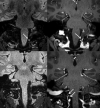

Intradural extramedullary foramen magnum enhancing lesions may be due to meningioma, nerve sheath tumor, aneurysm, or meningeal disease. In this clinical report of 14 patients, we describe a novel imaging finding within the foramen magnum that simulates disease. The lesion is hyperintense on 3D-FLAIR and enhances on 3D gradient-echo sequences but is not seen on 2D-TSE T2WI. It occurs at a characteristic location related to the posterior aspect of the intradural vertebral artery just distal to the dural penetration. Stability of this lesion was demonstrated in those patients who underwent follow-up imaging. Recognition of this apparently benign lesion may prevent unnecessary patient anxiety and repeat imaging.